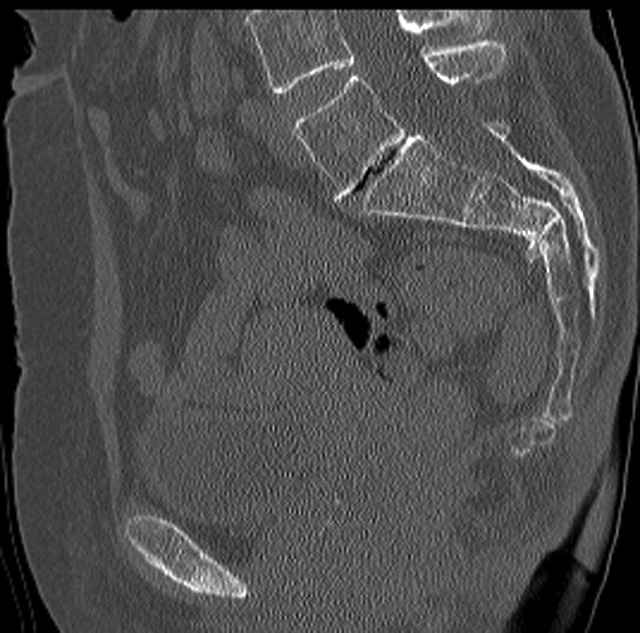

Pelvic CT Scan - 3 Months After Fall

Sacral Injuries

Ramus Fractures

Percutaneous Fixation

(B) Ramus-Retrograde

2 TransIliac-TransSacral

Upper Segment